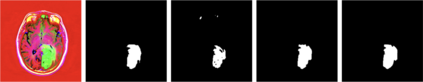

Medical imaging plays a crucial role in modern healthcare by providing non-invasive visualisation of internal structures and abnormalities, enabling early disease detection, accurate diagnosis, and treatment planning. This study aims to explore the application of deep learning models, particularly focusing on the UNet architecture and its variants, in medical image segmentation. We seek to evaluate the performance of these models across various challenging medical image segmentation tasks, addressing issues such as image normalization, resizing, architecture choices, loss function design, and hyperparameter tuning. The findings reveal that the standard UNet, when extended with a deep network layer, is a proficient medical image segmentation model, while the Res-UNet and Attention Res-UNet architectures demonstrate smoother convergence and superior performance, particularly when handling fine image details. The study also addresses the challenge of high class imbalance through careful preprocessing and loss function definitions. We anticipate that the results of this study will provide useful insights for researchers seeking to apply these models to new medical imaging problems and offer guidance and best practices for their implementation.